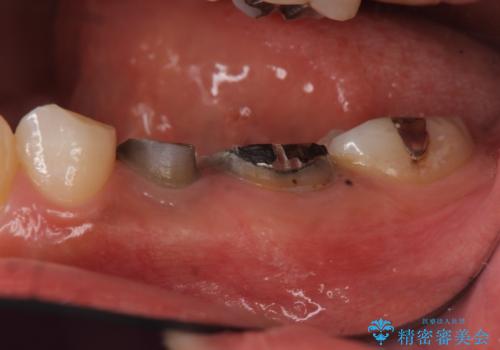

- 右下の歯を抜いた箇所に親知らずを矯正治療で移動できないかというご相談で来院。

欠損の部分にはブリッジまたはインプラント、義歯の選択肢がありますが、インプラント治療をご希望されました。

他院で抜歯後いらしたため、骨ができるのを待って、オペは2回法で行っております。

2回法の利点は、骨増成が確実であることと、FGGが可能で長期に安定した歯ぐきが得られることです。